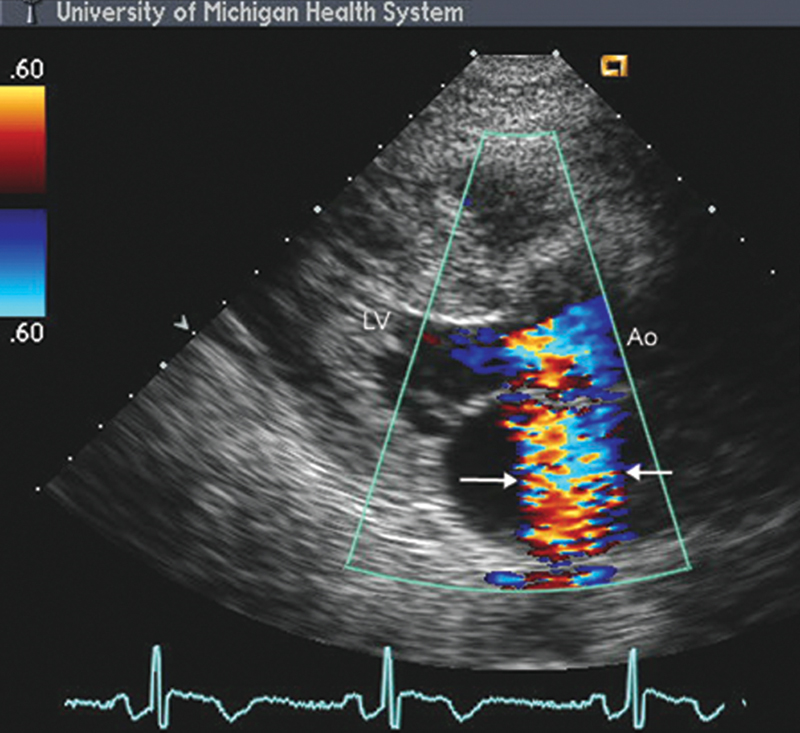

فحوصات تشخيصية لبعض امراض القلب والشرايين التاجية